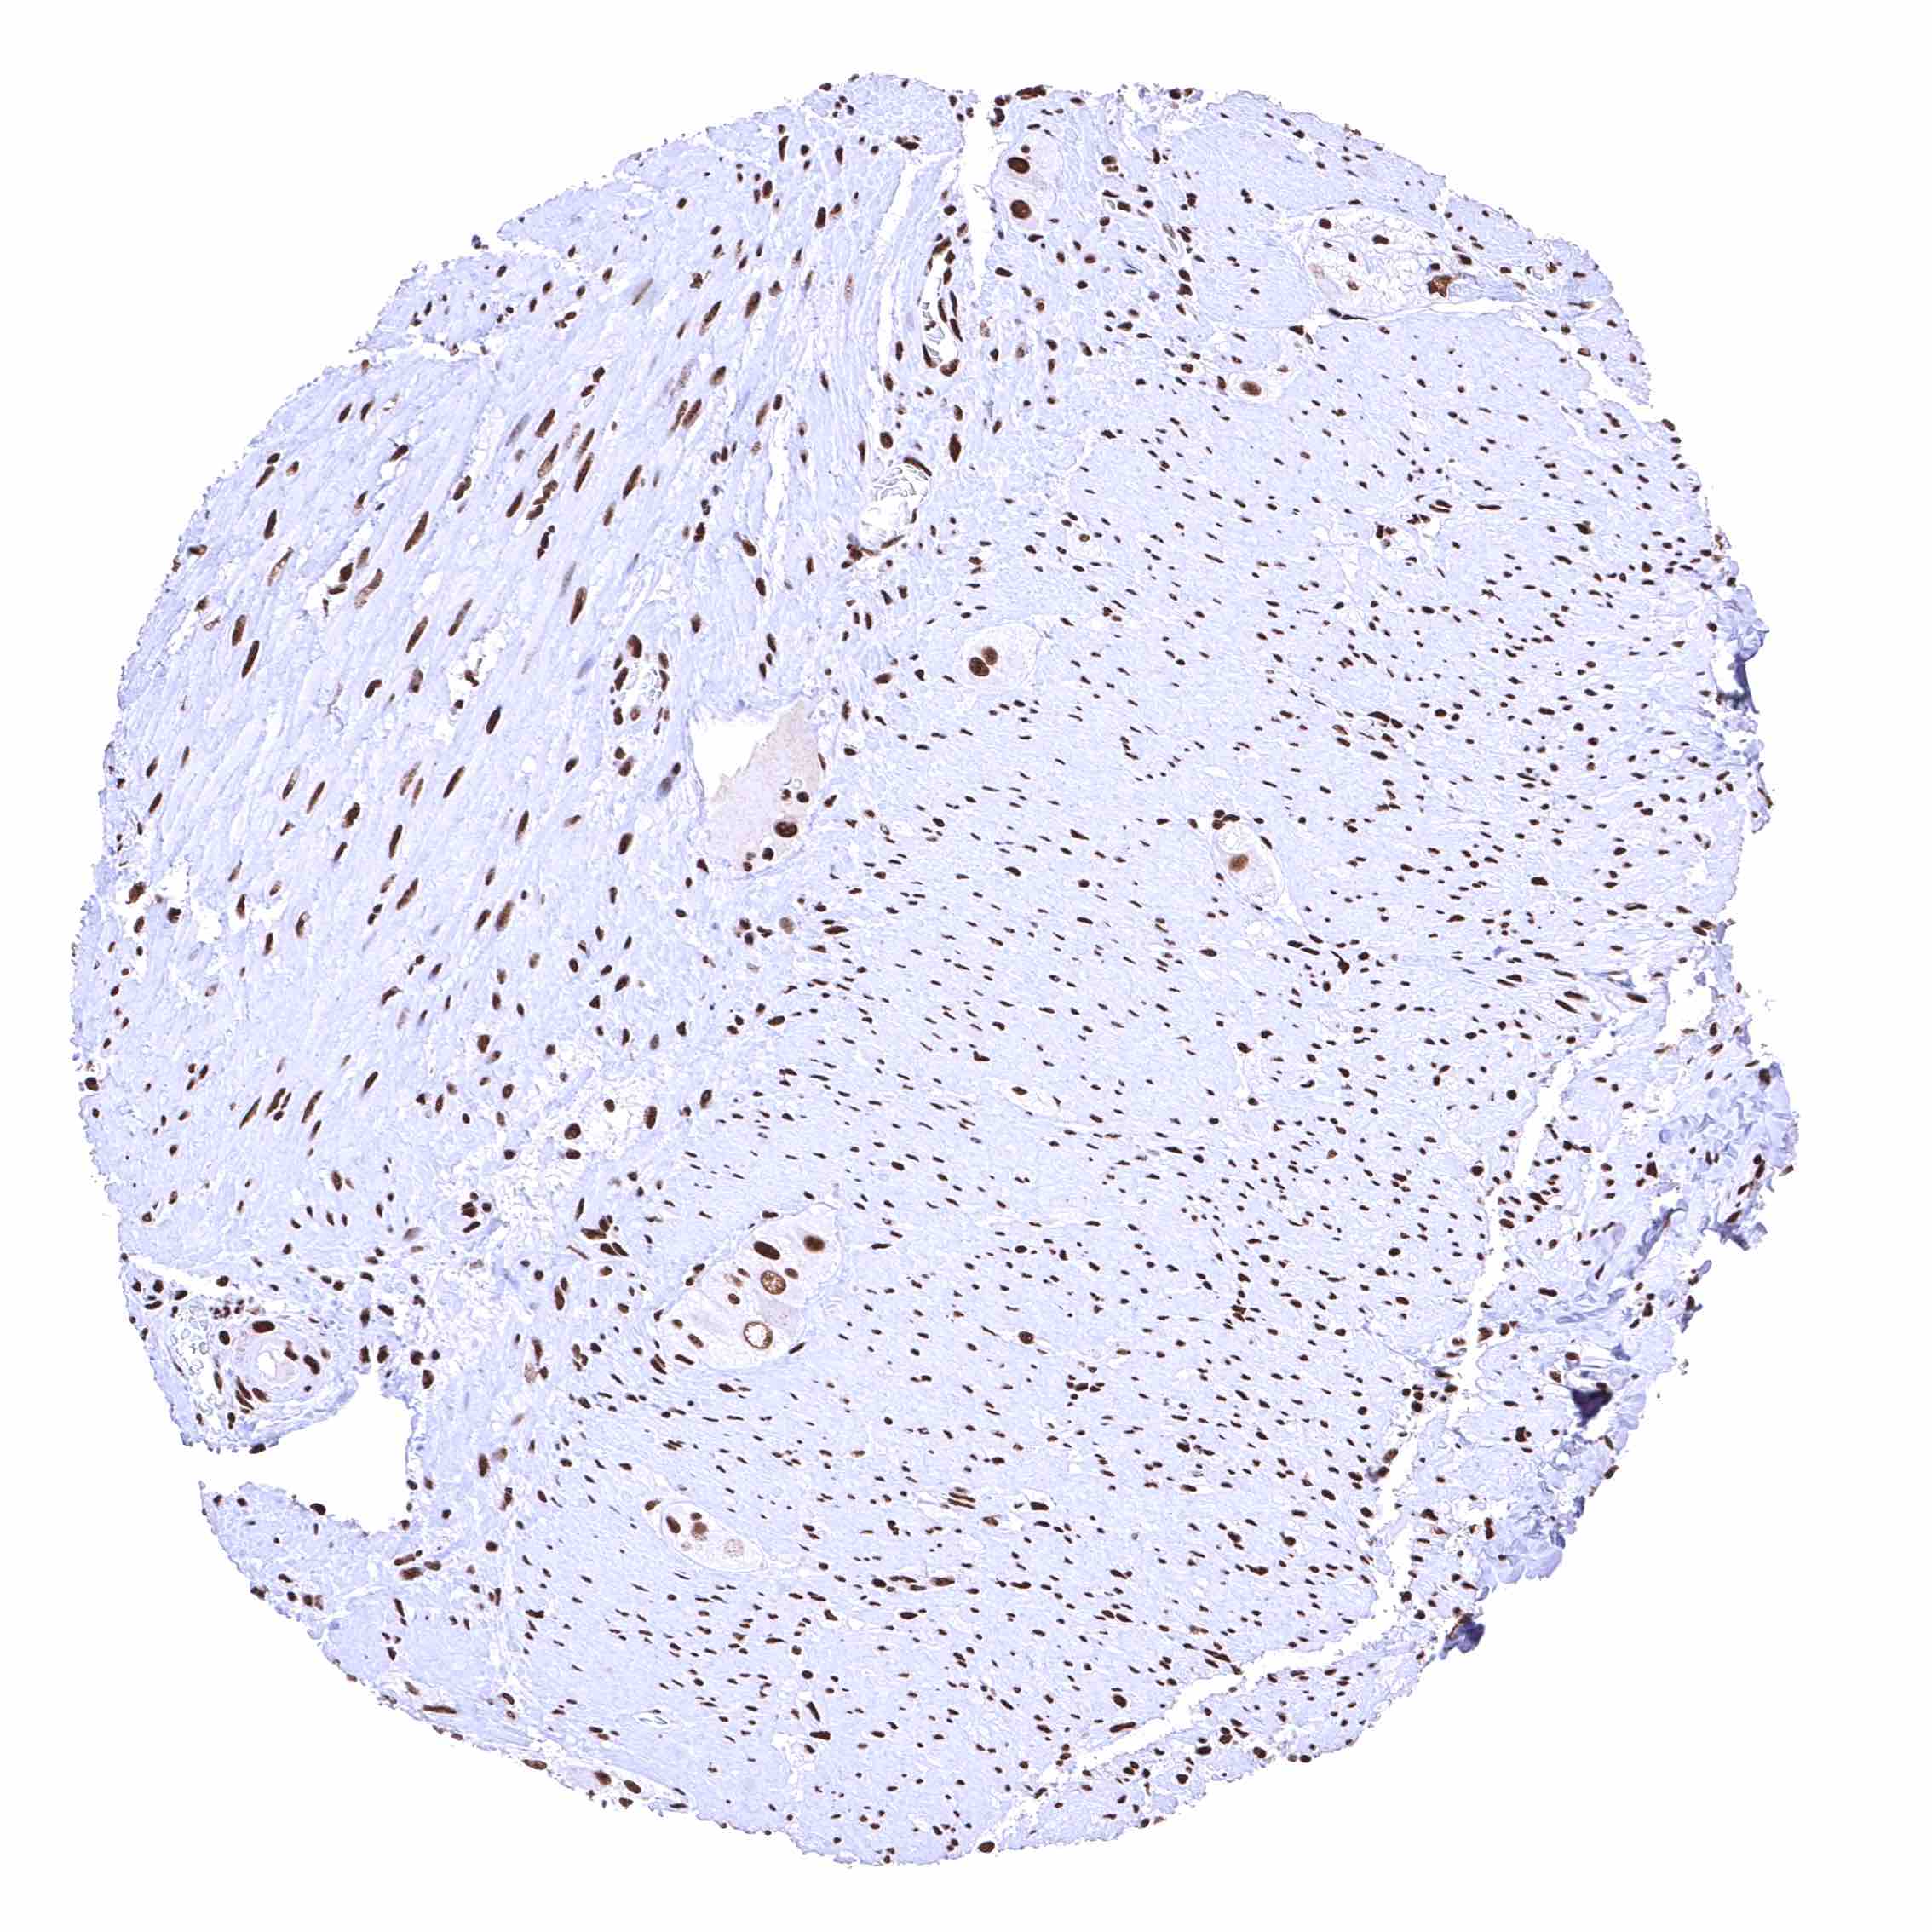

BRD4 antibody [HMV4275] HistoMAX™

Heart muscle – Distinct nuclear BRD4 staining of all cells. The additional cytoplasmic staining of some muscle cells may represent an antibody specific cross-reactivity.